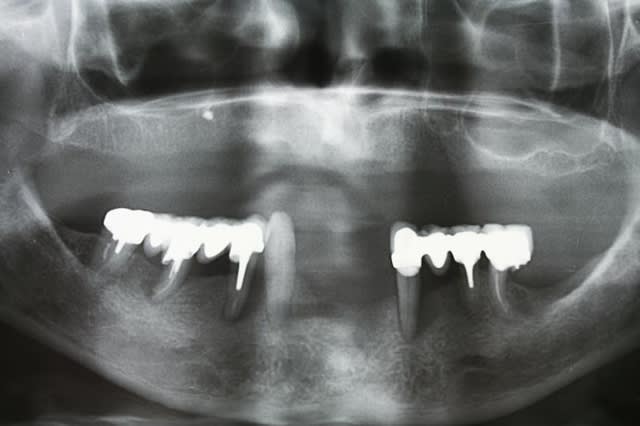

dans le style exotique..certes pas de MCI mais pas mal quand même.... adressé par un ami un peu dépassé par le cas qui se présentait... le travail était bien entendu la prothèse définitive... et de l'amalgame réunit les deux implants extrêmes...

K de philip vuyjiz - Eugenol

Dsc 0022 zyz4bz - Eugenol